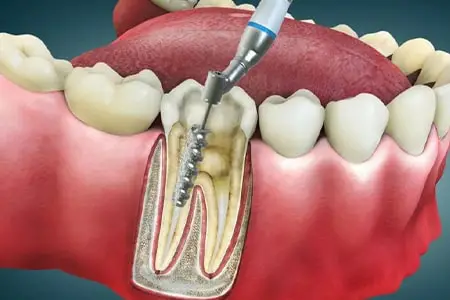

پاکسازی کانالها

در این مرحله تمام بافتهای عفونی و عصبهای آسیبدیده با دقت میکروسکوپی از داخل ریشه خارج میشوند.

پر کردن ریشه

فضاهای خالی داخل دندان با مواد زیستسازگار (گوتاپرکا) پر میشوند تا از ورود باکتریها جلوگیری شود